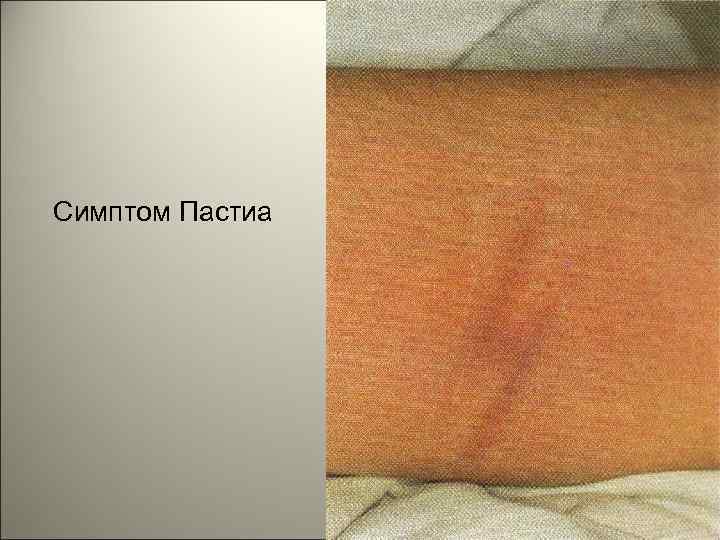

• На лице отмечаются яркая гиперемия щек и бледный носогубной треугольник. По краям румянца можно различить отдельные мелкоточечные элементы сыпи. В складках кожи (особенно в локтевых сгибах) отмечаются мелкие кровоизлияния, которые, сливаясь, образуют своеобразную насыщенную окраску складок (симптом Пастиа). 142

Симптом Пастиа 146